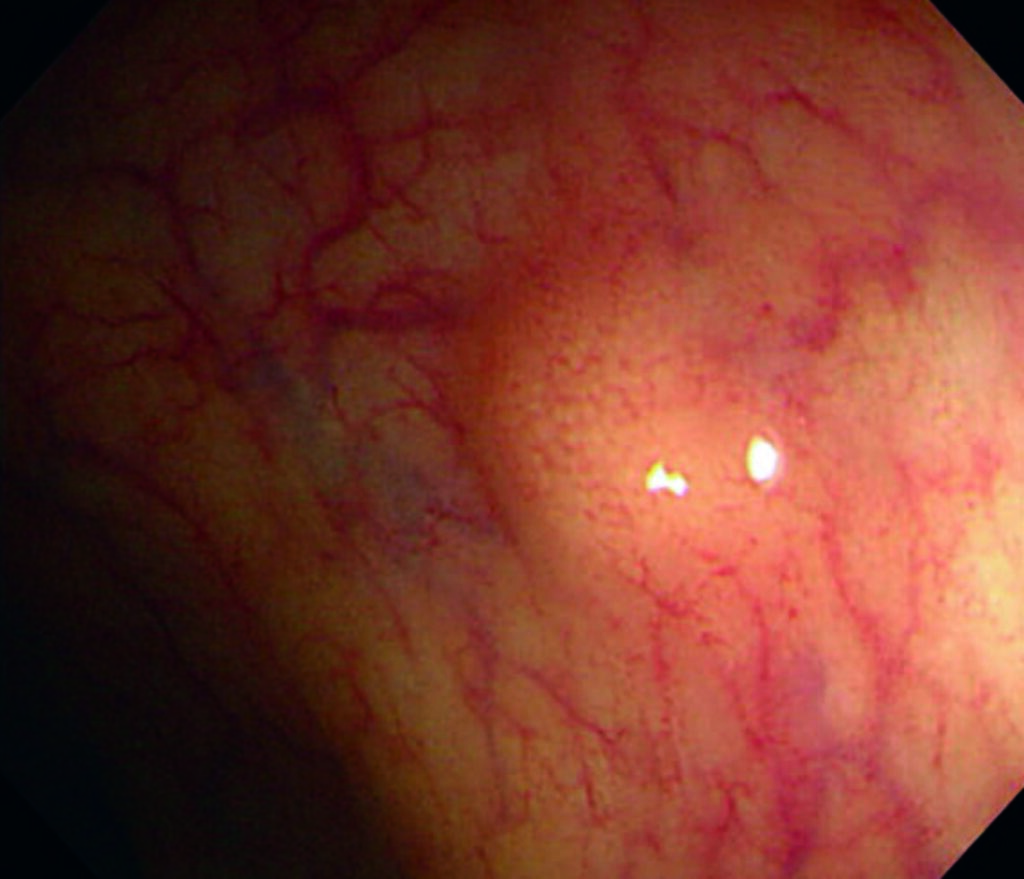

Los NET del recto suelen descubrirse también de manera incidental durante procedimientos endoscópicos, manifestándose como nódulos submucosos. Aquellos menores de 1 cm casi nunca desarrollan metástasis y pueden ser tratados de forma efectiva mediante resección local, ya sea endoscópica o transanal. En contraste, los tumores rectales de mayor tamaño (superiores a 1 o 2 cm) presentan un riesgo del 10% de diseminación, particularmente si invaden la muscular propia o presentan compromiso ganglionar. En estos casos, se recomienda una resección oncológica más extensa, siempre que el estado general del paciente lo permita.